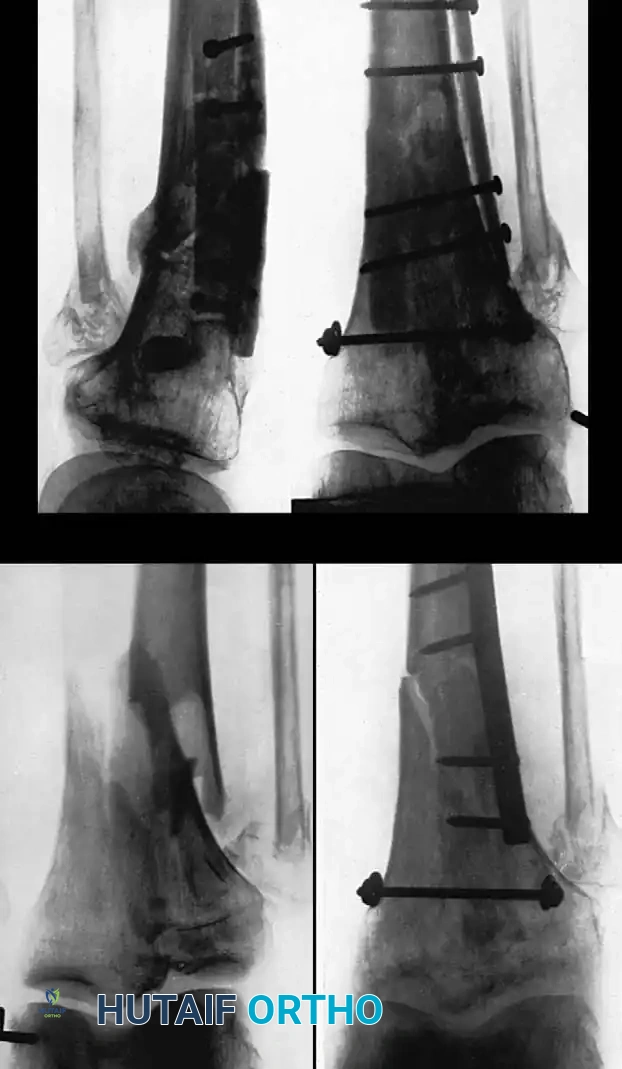

Medial Malleolus

A fracture of the medial malleolus occasionally fails to unite, especially after nonoperative (closed) treatment where periosteum or the deltoid ligament may interpose between the fracture fragments.

Surgery may be indicated for the few nonunions in which other serious complications of the fracture, such as advanced traumatic arthritis, are not seen on radiographs, and ideally if the injury is less than 2 years old. The standard surgical technique usually includes excision of the fibrous nonunion, application of autogenous bone grafts, and rigid internal fixation of the malleolar fragment.

When the nonunion is painful, it can be treated in one of three ways depending on the morphology of the fragment and the patient's functional demands:

- Bone Grafting and Fixation: When neither of the two previous treatments seems applicable (e.g., large fragment, young active patient, unstable mortise), formal bone grafting and internal fixation are indicated.

Technique 56-7: Sliding Graft for Medial Malleolus

- Exposure: Expose the nonunion through an anteromedial curved incision 10 cm long.

- Preparation: Reflect the periosteum anteriorly and posteriorly. Meticulously remove all interposed fibrous tissue from the nonunion site. Freshen the ends of the fragments using a curette or high-speed burr, but remove no bone from their deeper (articular) edges to avoid joint penetration. Carefully hollow out the distal fragment to receive the graft.

- Graft Harvest: Beginning at the nonunion and using an oscillating motor saw, harvest a cortical graft approximately 4 cm long and 1 cm wide from the proximal tibial fragment.

- Graft Placement: Displace (slide) the graft distally across the nonunion site and into the prepared trough in the distal fragment.

- Fixation: Hold the distal fragment in its precise anatomic position, restoring the mortise. Transfix the fragments and the sliding graft with a fully threaded or partially threaded 4.0 mm cancellous lag screw.

- Augmentation: Place cancellous bone chips (harvested from the proximal metaphysis) around the graft site to enhance osteoconduction.

- Closure: Confirm the position of the graft, the screw, and the joint space with intraoperative fluoroscopy. Close the wound in layers.

Fig. 56-18 Nonunion of medial malleolus treated by sliding graft.

Postoperative Protocol: A non-weight-bearing cast is applied from the toes to just distal to the knee. At 2 weeks, sutures are removed, and a walking cast or rigid boot is applied. Partial weight-bearing is allowed during the next 2 weeks, advancing to full weight-bearing thereafter. The immobilization is discarded when radiographs confirm osseous union, typically at 8 to 10 weeks.